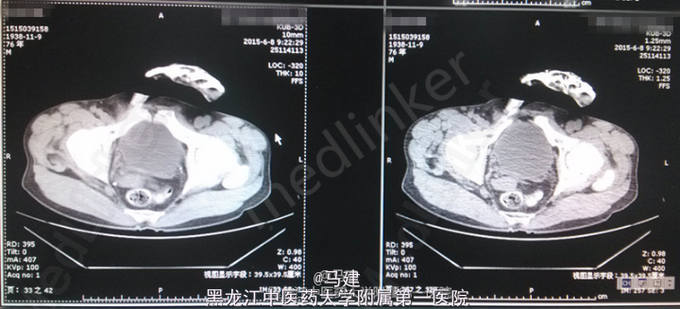

查体:T:36.2℃,P:64次/分,R:20次/分(规则),BP:138/83mmHg。神志清,精神可,全身浅表淋巴结无肿大,心肺腹未及明显异常,脊柱四肢活动自如。 专科情况:双肾区无明显压痛及叩击痛,输尿管行走区域正常,无压痛,膀胱叩诊呈浊音,无压痛,阴茎发育正常,无包茎或包皮过长,尿道外口正常,无狭窄、炎症分泌物,双侧阴囊对称,睾丸及附睾正常。前列腺直肠指检呈I°增大,中央沟存在,质地正常,无触痛,无结节。 入院后检查:血常规:RBC 4.29*10^12/L,Hb 123.0g/L,HCT 37.7%,WBC 3.55*10^9/L;尿常规:红细胞(+),红细胞计数 101.0/μl;尿培养:无细菌生长;三次尿脱落细胞学检查中一次偶见可疑Ca细胞;泌尿系CT示膀胱右侧壁见大小约23*42mm的软组织密度影。